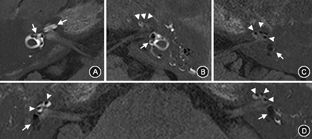

174例患者的耳蜗、前庭、半规管的外淋巴间隙均呈明显的高信号、对比剂钆增强影;耳蜗、前庭、半规管的内淋巴间隙呈低信号、无对比剂的区域,被高信号的外淋巴间隙包绕,可由此区分内外淋巴边界(图1)。174例患者均存在不同程度的EH,其中5例(2.9%)轻度积水(双耳均为轻度),40例(23.0%)中度积水,129例(74.1%)重度积水,中重度积水占97.1%。其中139例为单耳EH,35例存在双耳EH。139例单耳EH患者中,前庭无或轻度积水19例(13.7%),中度积水38例(27.3%),重度积水82例(59.0%);耳蜗轻度积水24例(17.3%),中度积水51例(36.7%),重度积水64例(46.0%)。35例双耳EH患者中,首发症状耳前庭无或轻度积水2例(5.7%),中度积水6例(17.1%),重度积水27例(77.1%);耳蜗轻度积水2例(5.7%),中度积水16例(45.7%),重度积水17例(48.6%)(表2)。双耳积水患者的首发症状耳的积水中重度比例高于单耳积水患者(前庭:94.2%比86.3%,耳蜗:94.3%比82.7%),但差异均无统计学意义(均P>0.05)。

注:A:前庭、耳蜗无/轻度积水;B:前庭、耳蜗中度积水;C:前庭、耳蜗重度积水;D:同一患者双侧前庭、耳蜗均重度积水;箭头示低信号区域为前庭内淋巴间隙,三角示低信号区域为耳蜗内淋巴间隙